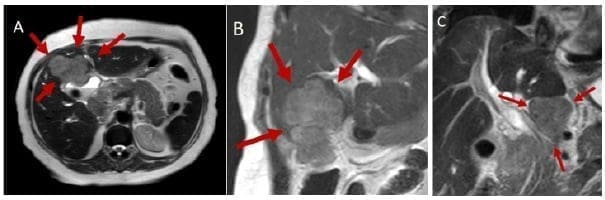

La ecografía abdominal debe hacer sospechar un CVB cuando hay engrosamiento focal e irregular de la pared de la vesícula o cuando el espesor es mayor de 10 mm. La TC y la RNM son más útiles para evaluar la extensión de la enfermedad o cuando hay masas vesiculares de buen tamaño 49 (Figuras 2 y 3).

Figura 2. Resonancia magnética que muestra gran masa en la vesícula biliar

con infiltración al hígado (A y B) y conglomerado ganglionar celíaco (C).